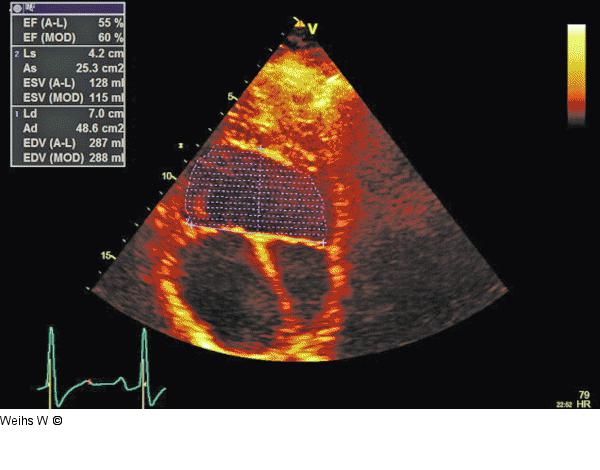

Abbildung 6: Linksventrikuläre Volumina - EF Die Berechnung der linksventrikulären Volumina bzw. der Auswurffraktion (EF) ist aufgrund der geänderten Geometrie unzulässig. |

Die Berechnung der linksventrikulären Volumina bzw. der Auswurffraktion (EF) ist aufgrund der geänderten Geometrie unzulässig. |